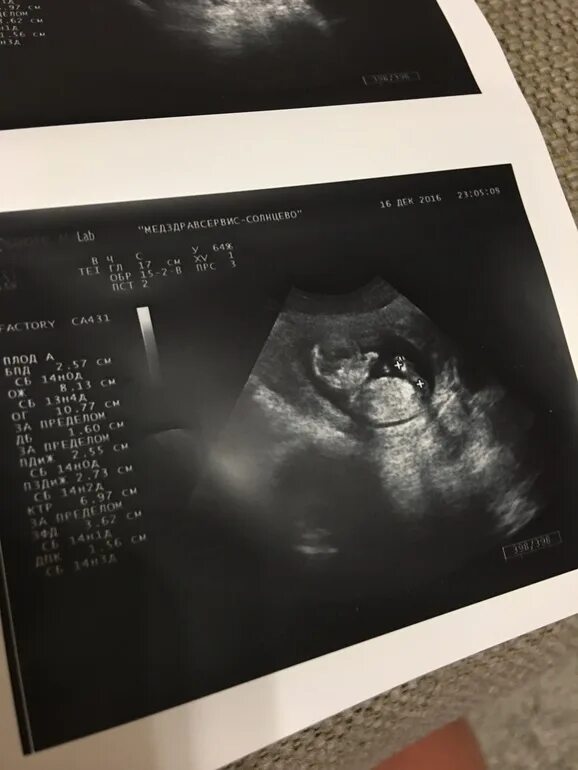

Ктр при узи что это